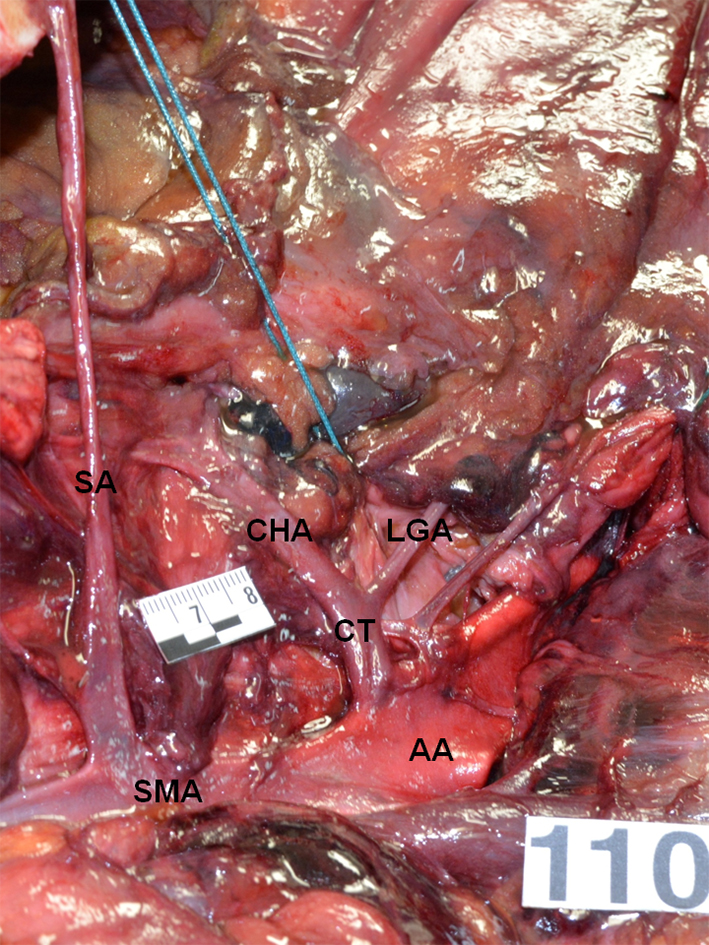

| CT: celiac trunk; LGA: left gastric artery; CHA: common hepatic artery; SA: splenic artery; AA: abdominal aorta; SMA: superior mesenteric artery. | ||||||||